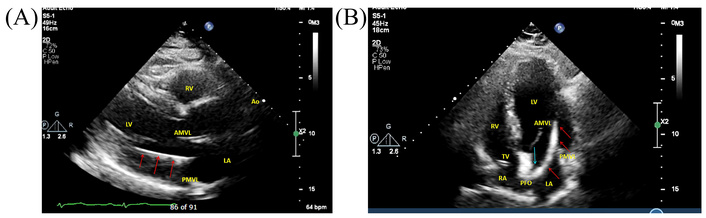

Seventeen months later, in December 2024, the patient presented with worsening dyspnoea. TTE performed during evaluation demonstrated improvement in left ventricular systolic function (LVEF 45–50%), likely reflecting optimisation of guideline-directed heart failure therapy and natural variability in ejection fraction measurements rather than a direct effect of ICD implantation. The dyspnoea was attributed to fluctuations in heart failure symptoms, as there was no valvular obstruction, embolic event, or device malfunction identified. Unexpectedly, the ICD lead was visualised crossing the interatrial septum and mitral valve into the left ventricle via a PFO (Figure 4).

Transthoracic echocardiogram. (A) Parasternal long-axis view demonstrating the ICD lead (red arrows) traversing the mitral valve into the LV. (B) Apical four-chamber view showing the ICD lead (red arrows) traversing the PFO (blue arrow), LA, and mitral valve into the LV. AMVL: anterior mitral valve leaflet; Ao: aorta; ICD: implantable cardioverter defibrillator; LA: left atrium; LV: left ventricle; PFO: patent foramen ovale; PMVL: posterior mitral valve leaflet; RA: right atrium; RV: right ventricle; TV: tricuspid valve.